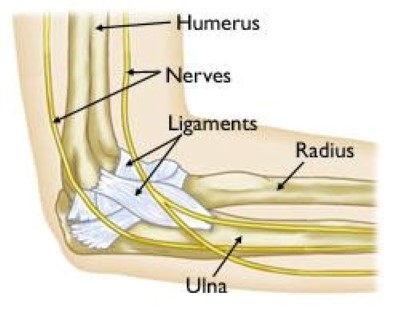

elbow joint anatomy

Bones of the elbow joint include the humerus (upper arm bone) and the ulna and radius of the forearm. Ligaments hold the elbow joint together and prevent dislocation.

The elbow is a complex joint formed by the joining of three bones:

• The humerus (upper arm bone)

• The ulna (forearm bone on the pinky finger side)

• The radius (forearm bone on the thumb side)

The surfaces of the bones where they meet to form the elbow joint are covered with articular cartilage, a smooth substance that protects the bones and acts as a natural cushion to absorb forces across the joint.

A thin, smooth tissue called synovial membrane covers all remaining surfaces inside the elbow joint. In a healthy elbow, this membrane makes a small amount of fluid that lubricates the cartilage and eliminates almost any friction as you bend and rotate your arm.

On the inner and outer sides of the elbow, ligaments (collateral ligaments) hold the elbow joint together and prevent dislocation.

The elbow joint is surrounded by muscles on the front and back sides. In addition, the three major nerves that cross the elbow joint are located close to the joint surfaces and capsule and must be protected during arthroscopic surgery.